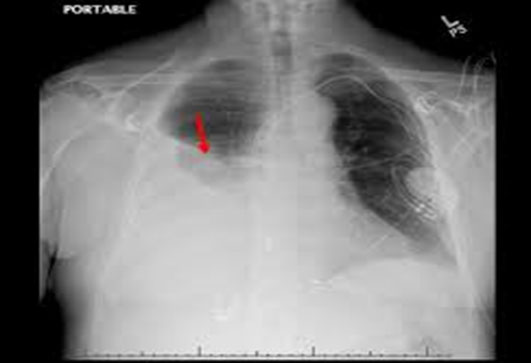

Pleural effusion is a medical condition characterized by the abnormal accumulation of fluid in the pleural cavity, the space between the membranes that surround the lungs. This condition can cause discomfort, breathing difficulties, and potentially life-threatening complications. To manage pleural effusion effectively, medical professionals often employ a procedure called chest tube insertion. In this blog, we will explore the causes, symptoms, and treatment options for pleural effusion, with a specific focus on the role of chest tubes.

The pleural cavity normally contains a small amount of fluid that helps lubricate the surfaces between the lungs and the chest wall, allowing smooth movement during breathing. However, when an imbalance occurs between the production and absorption of this fluid, pleural effusion can develop. There are several causes for pleural effusion, including: